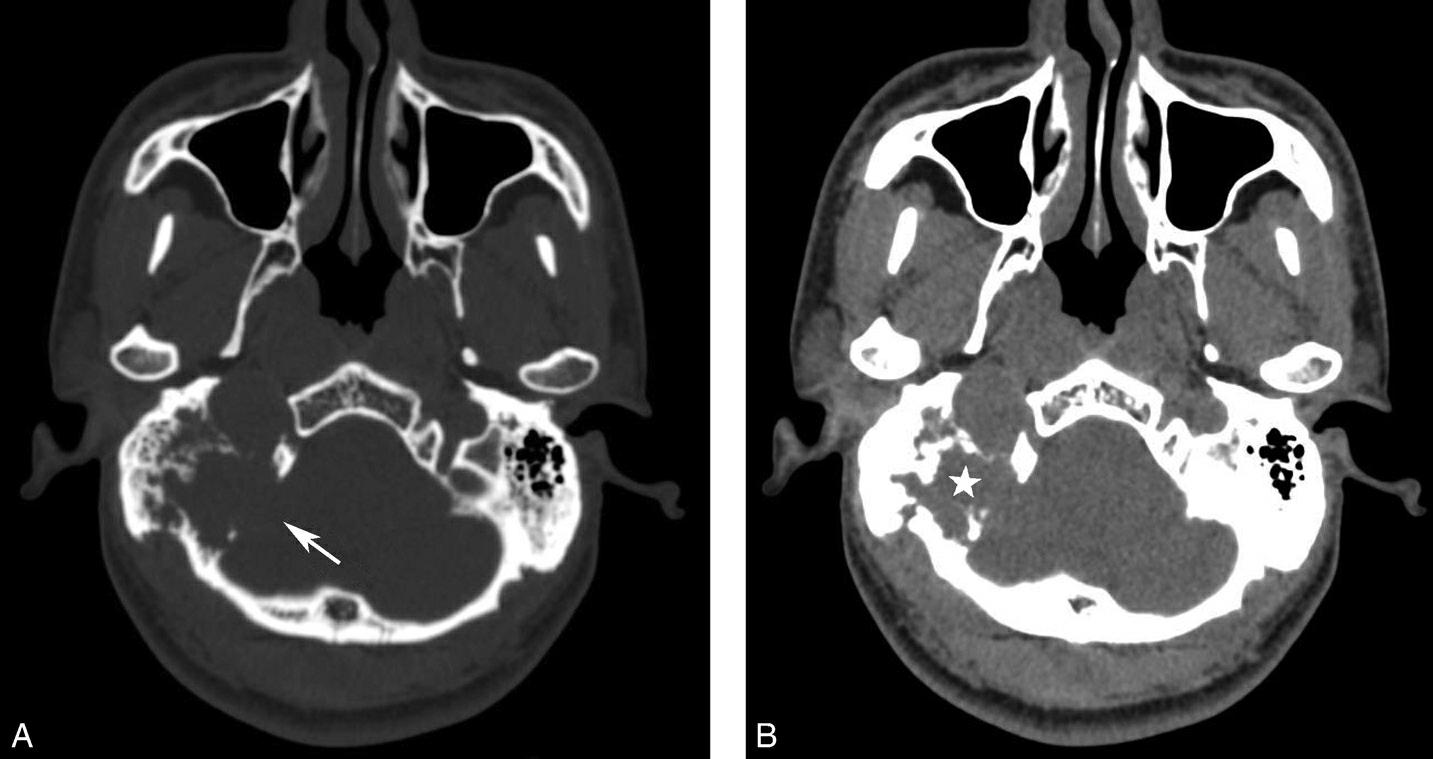

破裂孔、卵圆孔、棘孔及斜坡等均为重要的解剖结构,临床常见疾病如鼻咽癌常侵犯上述结构(图1-2-3)。颈静脉孔区较常见的肿瘤为颈静脉球瘤,常伴有颈静脉孔及其邻近骨质的破坏(图1-2-4)。

图1-2-3 鼻咽癌颅底骨质破坏

A.横断面;B.横断面(骨窗)

骨窗示左侧岩尖、斜坡、左侧蝶骨大翼骨质破坏、受侵(白箭),肿瘤经破裂孔侵入颅内(黑箭头)